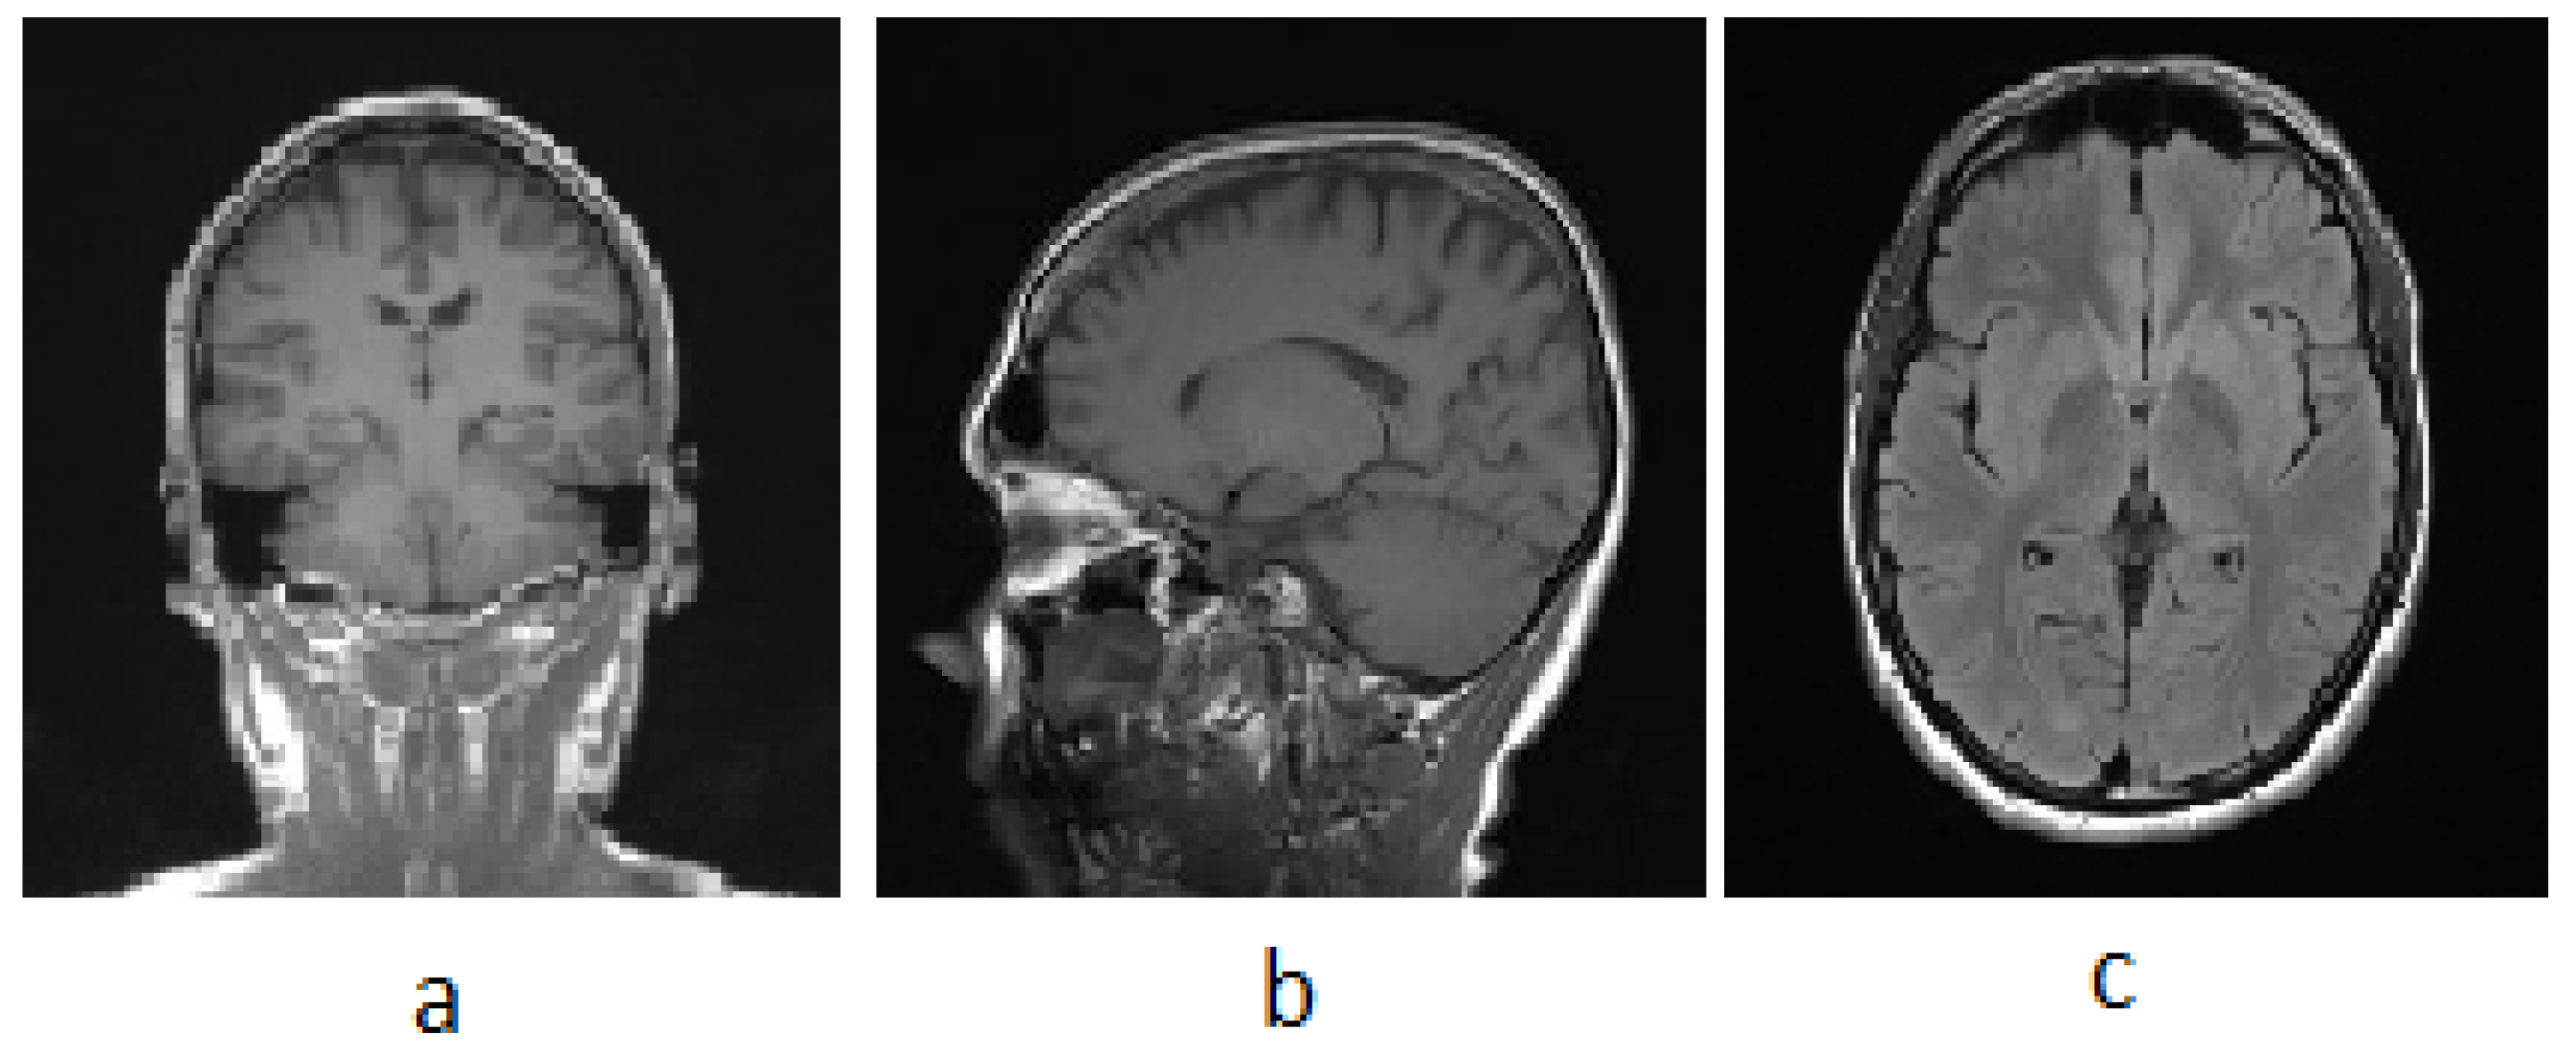

3.1. MRI

| T1 | T2 | Flair | |

|---|---|---|---|

| White Matter | Bright | Dark | Dark |

| Gray Matter | Gray | Dark | Dark |

| CSF | Dark | Bright | Dark |

| Tumor | Dark | Bright | Bright |